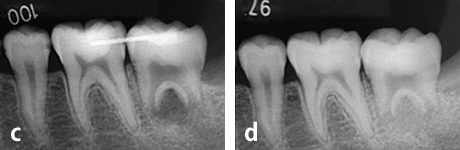

第二大臼歯部への親知らずの移植

a、b: 治療前。16歳、少女。

第二大臼歯が吸収を受けており保存が不可能でした。そこで、隣接する親知らずを同部へ移植することにしました。

c : 移植直後

d : 移植後3ヶ月